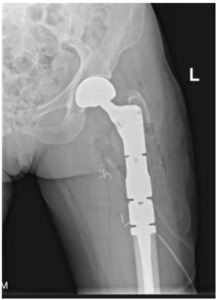

The surgeon must decide the appropriate procedure when a patient meets operative indications. The intervention must provide stability for the remainder of the patient’s life, minimize revision rate,82 and maximize time after recovery for them to enjoy their functional improvements. Surgical options include arthroplasty, intramedullary nailing, and plating.83 Any considerable metastatic disease in the femoral head indicates arthroplasty. Hemiarthroplasty versus total hip arthroplasty depends largely on the surgeon’s judgment regarding acetabular disease, underlying arthritic change, life expectancy, functional status, anticipated hip stability, and other factors. The conversion rate from hemiarthroplasty to total hip arthroplasty for acetabular wear in patients with metastatic disease is extremely low (1%), suggesting that the durability of hemiarthroplasty in these patients is more than acceptable in most circumstances [Figure 3a-d].84

When the metastasis exists in the basicervical femoral neck or peritrochanteric area, debate exists over whether internal fixation or endoprosthetic replacement is the most appropriate surgical option. While traditionally, the majority of these patients would be treated with intramedullary nailing, a study of 298 patients conducted at Memorial Sloan Kettering Cancer Center showed an incidence of IM nail failure of approximately 6.1% at an average 14.7 months, and plating was associated with a 42% failure rate.85 Mechanical failure from tumor progression and persistent loadbearing through the implant usually occurs between 12 and 15 months,88,89 and patient survival after surgery is the most important factor in predicting revision.86 It must be remembered that nails and plates were designed for non-pathologic traumatic fractures with reliable healing potential, which cannot be assumed with pathologic fractures. Catastrophic implant failure or painful disease progression often requires conversion to proximal femoral replacement, which undermines the goal of providing the patient with a durable, revision-free construct [Figure 4].

With these failure rates of internal fixation in mind, along with improved patient survival achieved in recent years, the utilization of arthroplasty implants is increasingly justified.3 If patient survival is anticipated to be greater than 6-12 months, the surgeon should strongly consider performing a durable endoprosthetic reconstruction– either hemiarthroplasty or proximal femoral replacement– over internal fixation. Traditionally, these implants are cemented due to periprosthetic fracture risk, unreliable biologic fixation of press-fit stems in pathologic bone, and radiation exposure; over the last few years, a few articles have called this into question and suggested similar success rates of press-fit and cemented stems.87,88 The complications associated with these arthroplasties occur earlier and differ from the mechanical failures seen with internal fixation.89 They include wound complications, periprosthetic infection, dislocation, and aseptic loosening.90 Cemented stems also introduce the risk of bone cement implantation syndrome, a poorly understood and fatal complication involving hypoxia, hypotension, and/or unexpected loss of consciousness occurring around the time of cementation or prosthesis insertion.91,92 If the patient survives the first several months without suffering one of these complications, the implant survival rate of prosthetic reconstruction is favorable overall compared to internal fixation strategies (3.1% revision rate reported by Steensma et al.).85 This advantage must be weighed against the prolonged operative time, higher risk of immediate surgical complications, increased cost, and prolonged postoperative recovery.